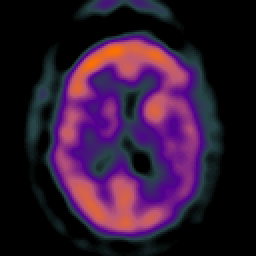

Subdural Hygroma,overlay -- Slice #28

[Home][Help][Clinical] Slice 28